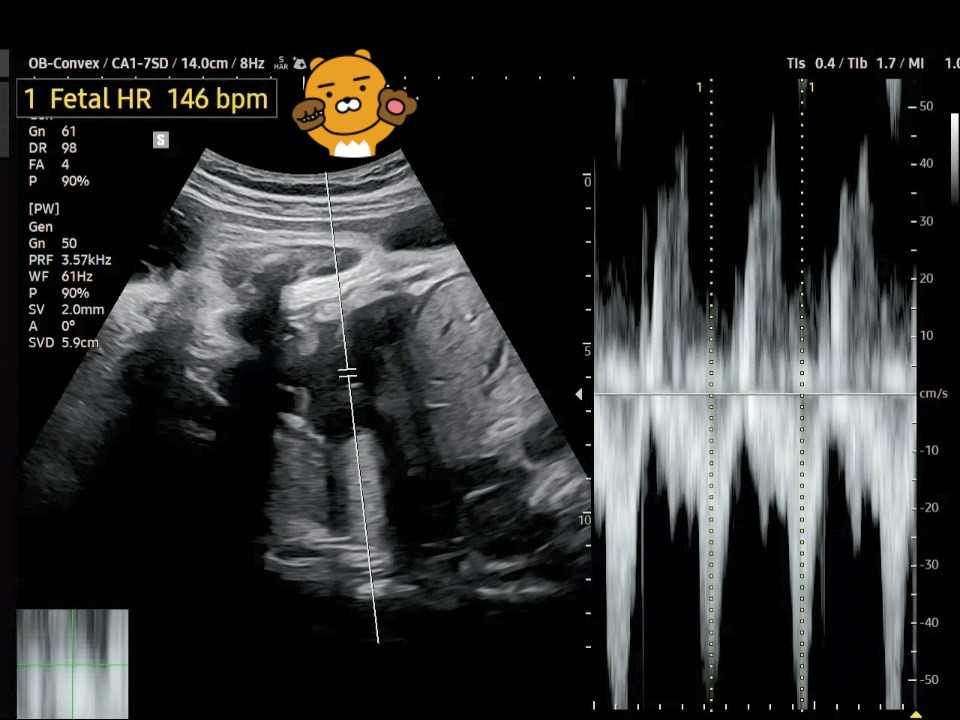

1. 심장박동수(Fetal Heart Rate)는 지난번 34주 차의 FHR과 동일하게 146 bpm입니다. 이 시기의 태아의 정상적인 심장박동수는 120~160 bpm이라고 합니다.

37주 FHR.jpg [37주 차 심장박동수]